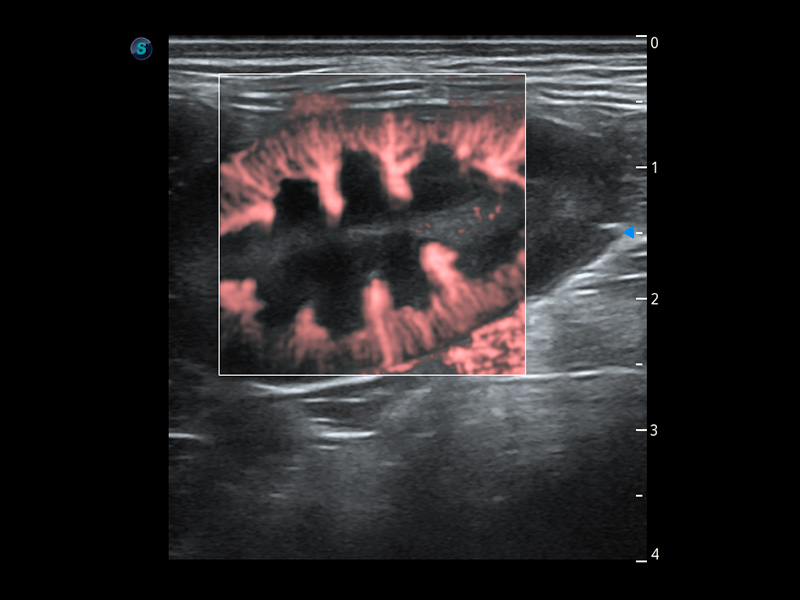

ProPet 60 作为一款高端台式动物超声设备,为动物医生的日常诊断提供了一系列贴合动物临床需求、解决临床实际问题的高级成像功能。凭借全系列高清探头,满足医生对腹部、心脏、生殖、浅表、肌骨等成像的所有需求,切实帮助您提升检查效率,提高诊断信心。

动物是人类最亲密的朋友和最值得信赖的伙伴。乐玩lewin国际也一直致力于探索动物专用的超声影像解决方案。 全新推出的ProPet系列,是乐玩lewin国际在动物超声影像智能化、专业化、精准化的一次跨越式革新。动物不能用言语来表述自己的不适,通过超声影像,ProPet系列搭建了动物医生与不同物种沟通的“桥梁”,为动物医生注入了“治愈之力”。